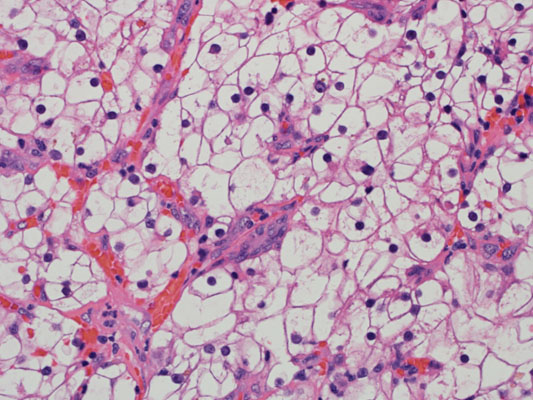

Consensus grade: WHO/ISUP grade 4